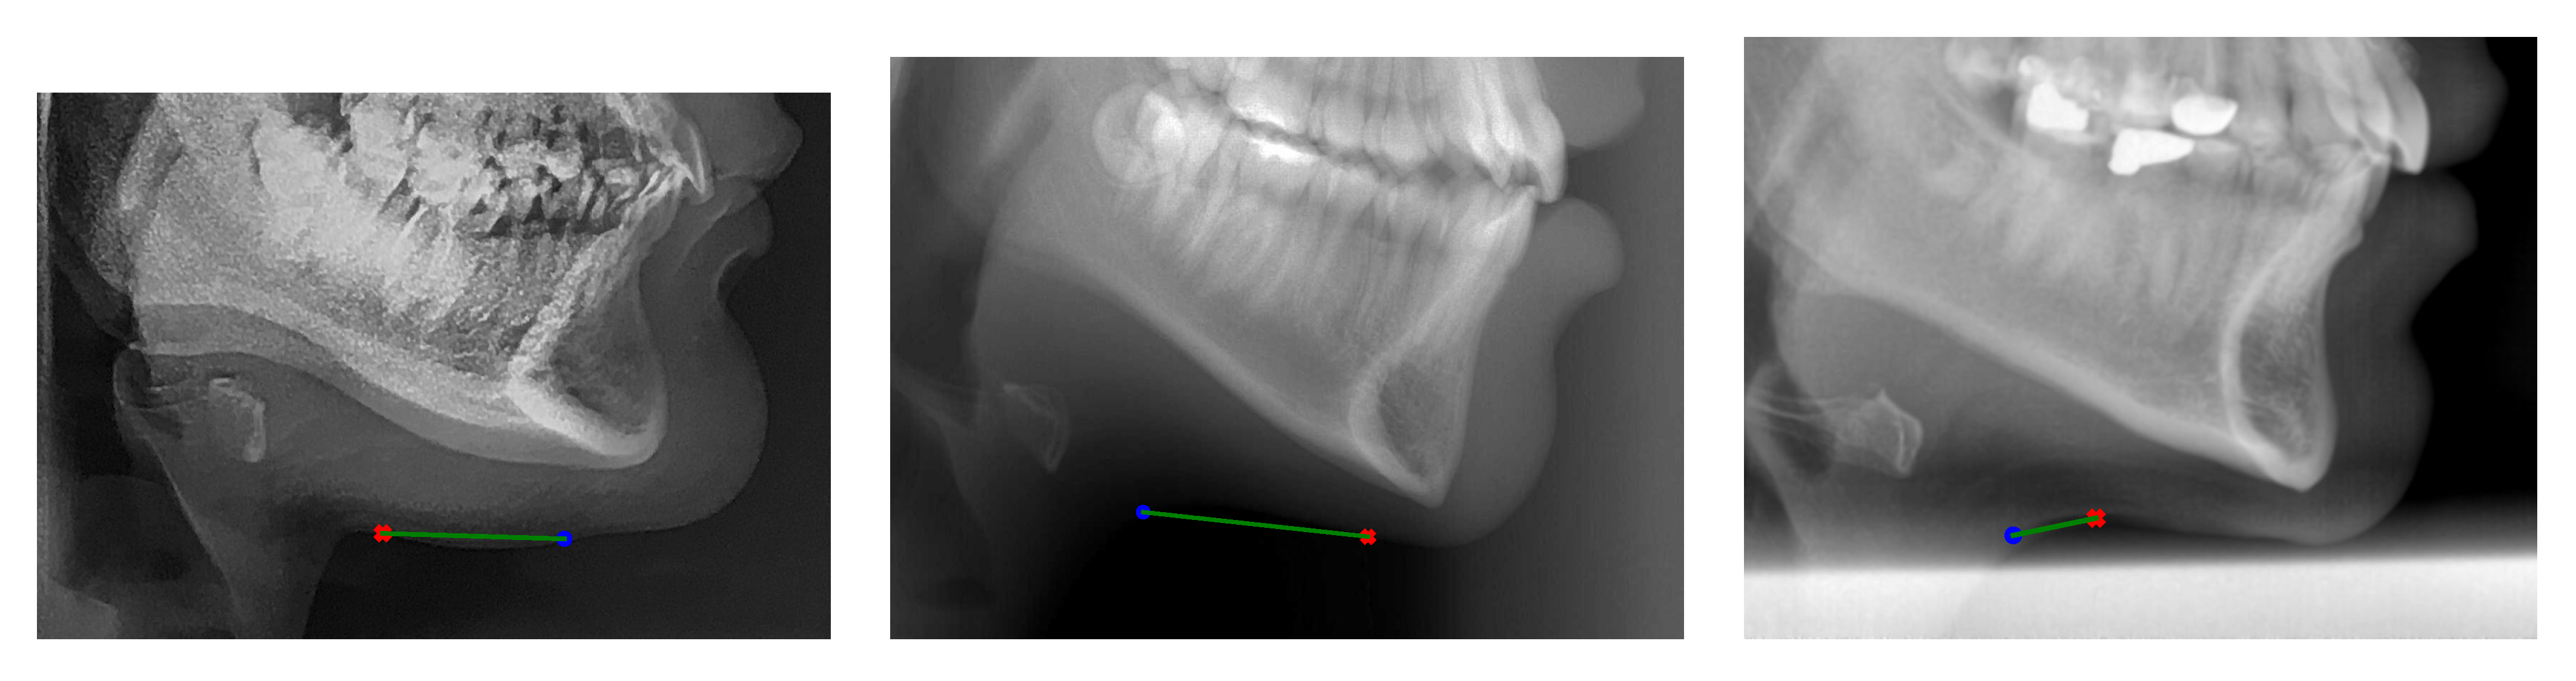

Figure 4 depicts the qualitative result of cephalometric landmarks’ detection by using our proposed SCN-EXT method on the AUDAX private database. Seventy-two estimated (denoted by a red x) and ground-truth (blue circle) cephalometric landmarks are superimposed on the skull X-ray image. The predicted and correct location of the landmarks are connected by the green line, where the following applies: the shorter the line, the lower the radial error. It can be noticed that, with the exception of the point on the throat, all the remaining cephalometric landmarks were localized extremely accurately.

Figure 4. Sample detection result, superimposed on the X-ray image from the AUDAX private database. Cephalometric landmarks were determined by the proposed SCN-EXT method. Estimated landmarks are denoted by a red x, while ground-truth locations are superimposed as blue circles.